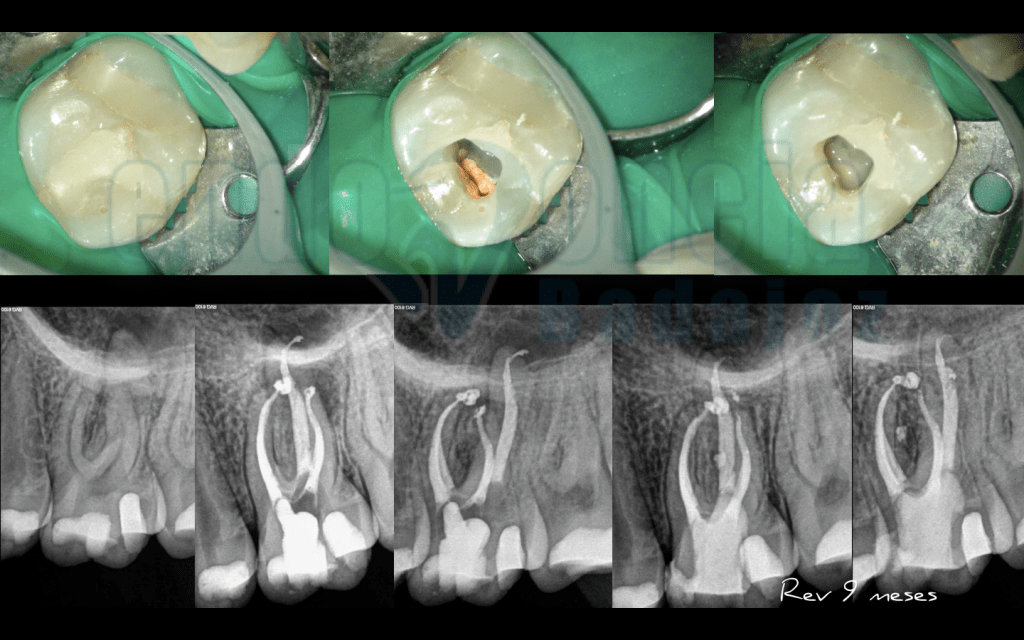

Caso 1:

Molar superior con Periodontitis Apical Asintomatica con lesión periapical que al los 9 meses va regenerando perfectamente.